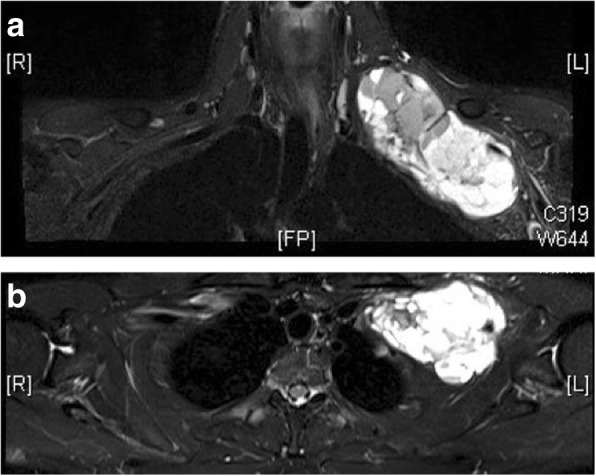

Fig. 2.

a Magnetic resonance T2 coronal image showing hyperintense tumor with hypointense regions in the supraclavicular and infraclavicular region. The subclavian artery can be seen entering the tumor and trunks and cords of brachial plexus can be seen in the cranial and lateral aspect of the lesion. b Magnetic resonance T2 transverse image showing tumor deforming first rib and lying close to apex of lung